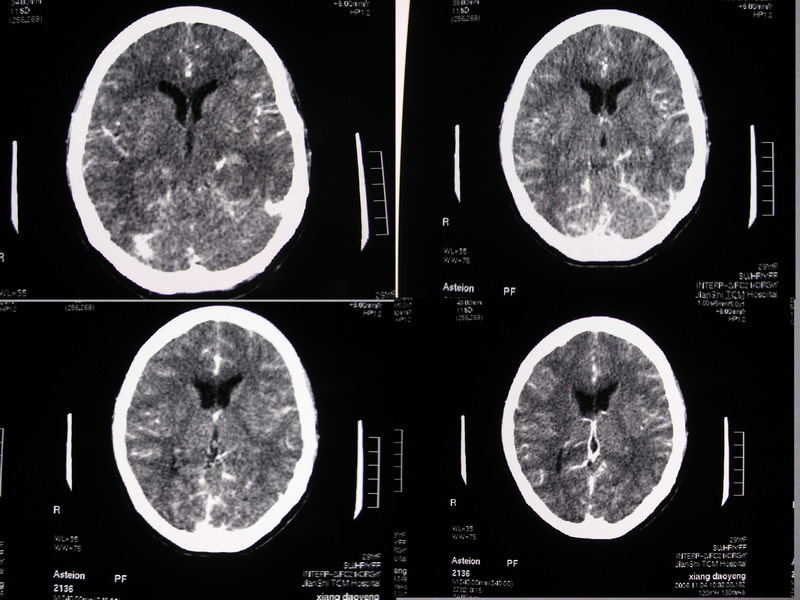

向××,女,29岁,二十天前高热,抗炎治疗后双眼斜视,肌无力,双下肢张力ii级。

奇怪啊!临床症状那么典型,为什么没有什么脑炎的迹象?二十天了,应该有表现的,是我眼拙?但小脑蚓部以及左侧颅中窝均属正常我应该没有看错,大汗淋漓!渴望老师们指点迷津!

除侧脑室额角轻度扩大外,余未见异常。

感觉胼胝体有异常,但看不出异常影像特征,建议行mri进一步确诊.

侧脑室稍扩大,余未见确切异常强化征,请结合脑脊液及脑脊髓mri检查

侧脑室稍扩大,余未见明显异常强化征。

双侧脑室有轻度扩大,增强看脑沟裂显示还是模糊的.时间较长应该考虑脑膜炎.